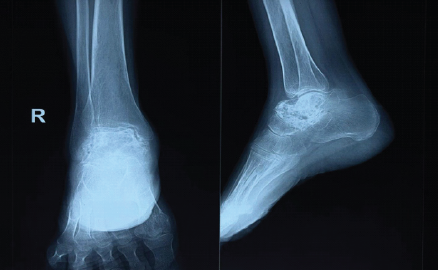

On follow-up, fluid from the lesion was aspirated under image guidance, and polidocanol injection was administered percutaneously at a dose of 3 mL/kg. The patient was advised full weight bearing along with oral analgesics and antibiotics. The patient showed improvement in pain and a decrease in the size of swelling 1 month later (Fig. 5). The polidocanol injection was repeated twice after a period of 6 months. After 2 years of follow-up, the patient had resolution of the swelling and minimal pain (Fig. 6).

Figure 6: 2-year follow-up radiograph of the right foot of the patient in anteroposterior and lateral view, showing sclerosis of the talus.